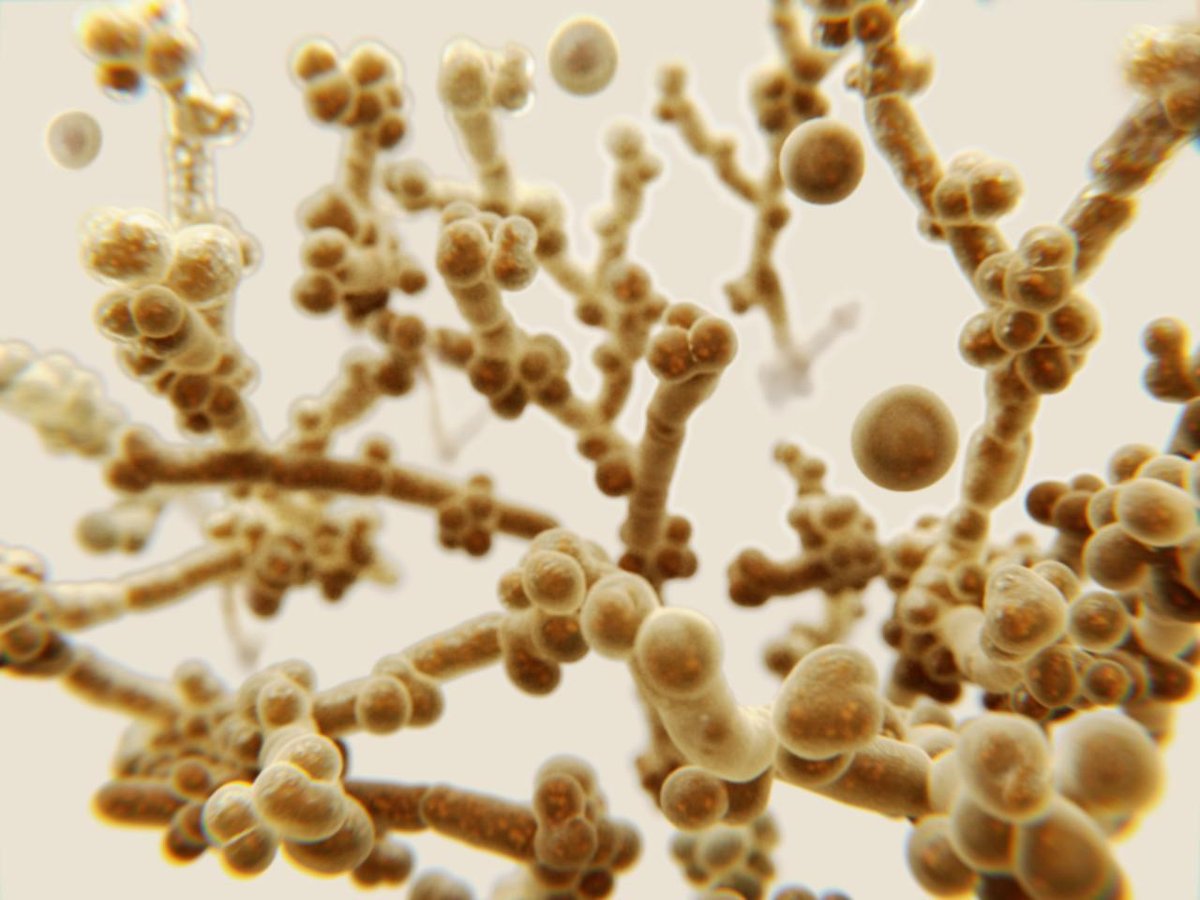

Zu der Gattung Candida gehören etwa 150 verschiedene Pilzarten, darunter C. auris und C. albicans.

Weiterhin zählen verschiedene Hefen zu den Pilzen. Hefepilze besiedeln vor allem Haut und Schleimhäute, können aber auch innere Organe befallen. Eine Gattung innerhalb dieser Hefen ist Candida. Infektionserkrankungen durch Hefepilze der Gattung Candida werden als Candidosen bezeichnet. Am weitesten verbreitet ist der Erreger Candida albicans.

Candida auris ist eine Pilzart, die zu den Hefepilzen der Gattung Candida gehört. Der Name “auris” ist abgeleitet vom lateinischen Begriff für “Ohr”, denn C. auris wurde 2009 erstmals in Japan im Zusammenhang mit einer Ohrinfektion beschrieben. Anscheinend gibt es die Art jedoch schon länger, da nachträglich in einer bereits 1996 entnommenen Probe der Erreger nachgewiesen wurde. Im letzten Jahr warnte die Weltgesundheitsorganisation WHO vor der gesundheitlichen Gefahr, die von unterschiedlichen Pilzinfektionen ausgeht – darunter auch Infektionen mit C. auris.